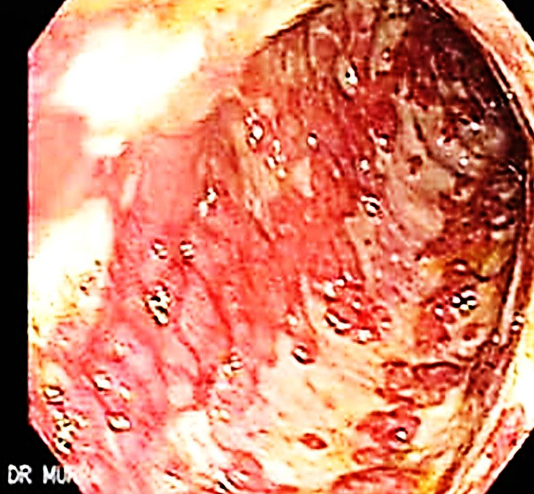

25 year old patient. Complaining of epigastric pain and dyspepsia since 1 month. Upper endoscopy showed duodenal ulcer as shown & H.pylori test was positive.

25 year old patient. Complaining of epigastric pain and dyspepsia since 1 month. Upper endoscopy showed duodenal ulcer as shown & H.pylori test was positive.

-

Name any 2 investigations used to diagnose H. pylori? Stool antigen test Urea breath test Z

-

Which combination of medicines is used to treat H. pylori infection?

- PPI’s - Omeprazole

- Clarithromycin

- Amoxicillin

-

Name any 1 complication of duodenal ulcer? Perforation